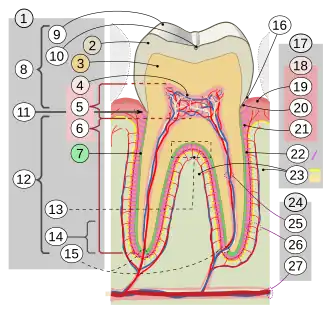

La gencive est la partie des muqueuses buccales qui assure le rôle de manchon étanche autour de chaque dent. Elle recouvre également l'os alvéolaire. Elle est la partie visible du parodonte.

La gencive peut se diviser en plusieurs parties :

- gencive marginale ou gencive libre.

En direction coronaire, la gencive se termine par le bord gingival libre aux contours festonnés. Cette gencive délimite, entre elle-même et la dent, un sillon appelé sulcus. - gencive attachée.

Cette gencive est attachée à l'os alvéolaire sous-jacent. - muqueuse libre.

En direction apicale, la gencive se continue avec la muqueuse alvéolaire lâche, de couleur rouge plus foncé, dont elle est séparée par une ligne de démarcation : la jonction muco-gingivale. - papille gingivale.

C'est la gencive située dans l'espace entre chaque dent.